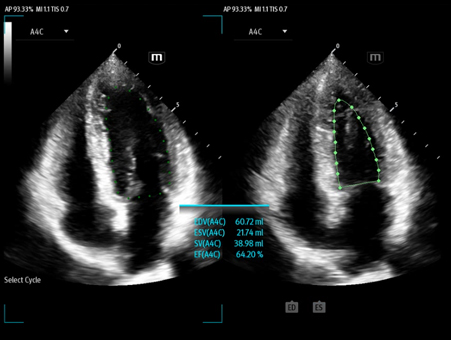

Mindray's Emergency Ultrasound Solutions address clinical challenges through a systemic approach. Those solutions cover the entire emergency care process from pre-hospital rescue and ambulance transport to ER treatment and in-hospital transfer. The versatility of Mindray Ultrasound shaping from Tablet system, Laptop-based system to Handheld Ultrasound system brings up the power of Ultrasound at the point of care. Clinical oriented smart features and protocols assist decisions with confidence.